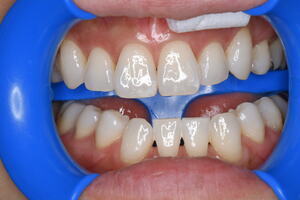

セレックインレーの不適合で虫歯が再発

適合が悪いため、虫歯が再発 虫歯を取り除き治療終了